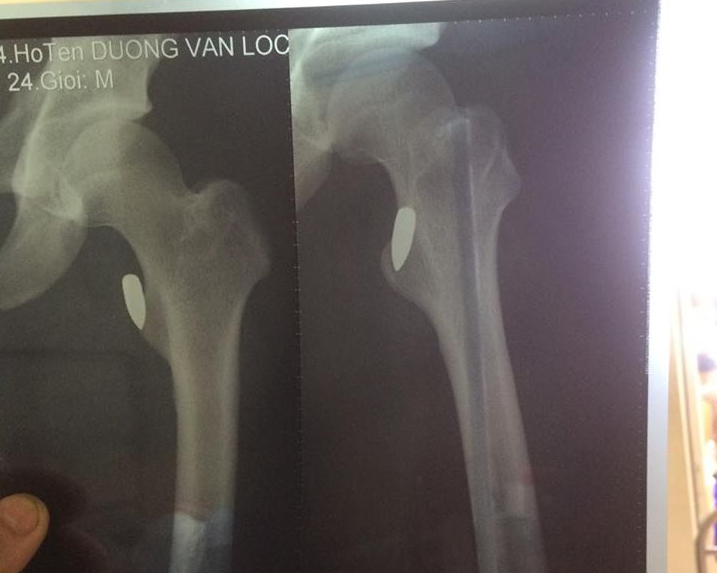

“Tôi cứ nghĩ nổ điện thoại nhưng đến khi vào viện cấp cứu, chụp X - quang, kết quả cho thấy đùi tôi bị trúng một viên đạn, rất may đầu đạn chỉ đi vào phần mềm, cách xương vài milimét. Thực sự, tôi cũng không biết viên đạn từ đâu đến”, anh Lộc kể lại.

Viên đạn mắc trong đùi anh Lộc.